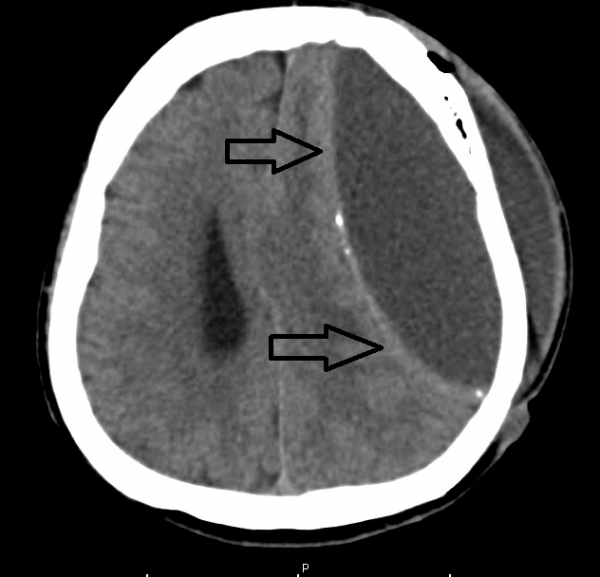

脑神经外科兼脊柱专科医生盛晓峰/中风开颅手术重植头骨发生排斥 厨师脑膜外脓肿

病人简介:发仔,54岁的厨师,因脑溢血中风做了开颅手术,重植头骨时发生排斥,引起脑膜外脓肿。

火速送院后,诊断是左脑严重溢血性中风,右侧身体瘫痪,情况危急。医生给他做了紧急开颅手术,移除一大块颅骨,降低颅内压,并取出血块。手术后,切除的颅骨并没有放回原位,而是保持头颅打开,以便提供空间降低颅内压,避免脑部水肿和再度出血。

我马上为发仔切除受到化脓性感染的颅骨,并仔细清洗积脓。好在脓肿只发生在脑膜外,没有伤及膜内,为了安全起见,发仔必须接受至少6周的抗生素治疗。